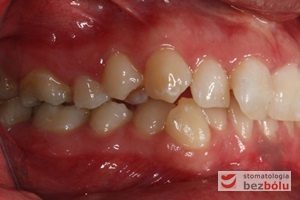

Pacjentka lat 22 zgłosiła się do naszej placówki celem podjęcia leczenia ortodontycznego. Głównym oczekiwaniem pacjentki była poprawa estetyki uśmiechu oraz brak ekstrakcji zębów na drodze do jej uzyskania. Ze względu na liczne stłoczenia zębów w górnym i dolnym łuku, dość duży materiał zębowy w porównaniu z bazą kostną, a także zgryz przewieszony boczny prawostronny po dokładnej analizie cefalometrycznej oraz analizie modeli diagnostycznych zastosowano leczenie bezekstrakcyjne z wykorzystaniem strippingu jako alternatywy dla usuwania zębów, mającego na celu uzyskanie miejsca w łuku na uszeregowanie zębów. Po fazie aktywnego leczenia trwającego 18 miesięcy zastosowano leczenie retencyjne w postaci szyny retencyjnej w łuku górnym oraz retainera stałego w łuku zębowym dolnym klejonego od kła do kła.